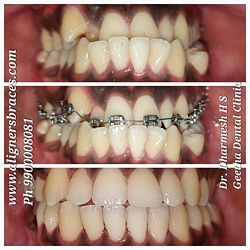

Case No: 26

Malocclusion Type: Anterior Cross Bite

Mechanics: Self-Ligating Appliance (3M Smart Clip) Maxillary arch

MBT Mechanics (3M) Mandibular arch

Treatment: Dental Class I Malocclusion with anterior crossbite treated using Different Appliance in the upper and lower arches.